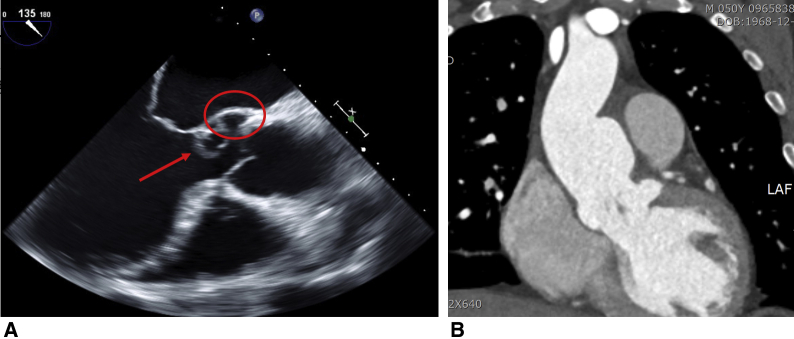

A 50-year-old man with a 6-month history of progressive dyspnea and chest discomfort presented to the emergency department. Chest radiography showed pulmonary edema and marked cardiomegaly. He had a history of recurrent oral aphthosis and scleritis. Echocardiography showed a left coronary cusp that was nearly detached from the aortic valve annulus, with mass-like conglomeration, and a pseudoaneurysm was observed at the ventriculo-aortic junction below the left coronary cusp (Figure 1, A). Moreover, marked aortic wall thickening with a saccular aneurysm from the left-right coronary commissure through the lesser curvature of the ascending aorta was also noted (Figure 1, B) on computed tomography. His preoperative C-reactive protein level and erythrocyte sedimentation rate were 2.94 mg/dL (normal range < 0.5 mg/dL) and 57 mm/h (normal range <10 mm/h), respectively. Cardiac involvement in BD was strongly suspected. Ethical committee approval was waived because of the study nature. Informed consent for the publication was obtained from the patient.

Figure 1.

A, Preoperative midesophageal long-axis view of transesophageal echocardiography: The left coronary cusp was nearly detached from aortic valve annulus with a mass-like conglomeration (arrow), causing severe aortic valve regurgitation. A pseudoaneurysm was formed at the ventriculo-aortic junction below the left coronary cusp (circle). All of these findings strongly suggested cardiac BD. B, Coronal section of preoperative computed tomography scan showed a saccular aneurysm from left-right coronary commissure through lesser curvature of ascending aorta with prominent inflammatory thickening of aortic wall by chronic vasculitis in cardiac BD.